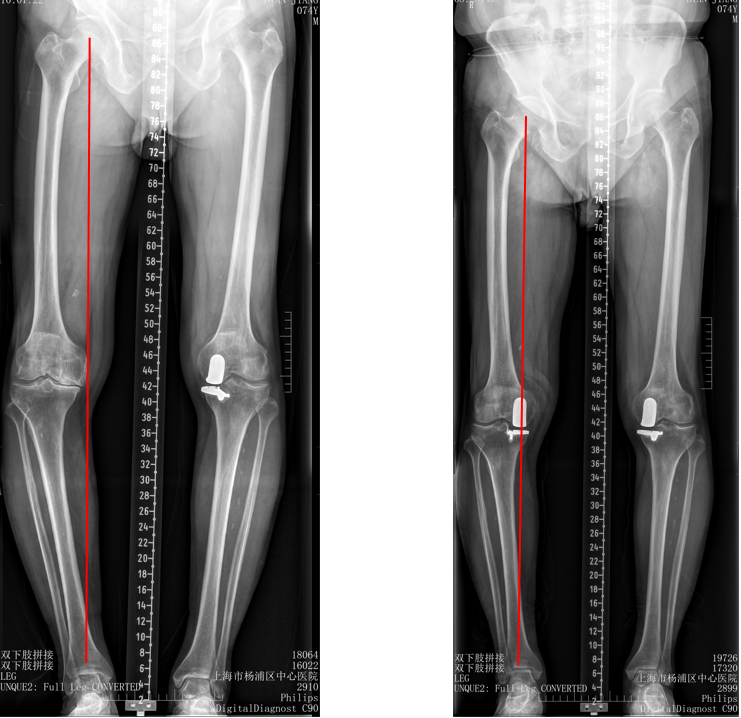

五、一期双单髁置换LINK:registered: SLED假体位置

双间室OA行Bi-UKA

正位片标准胫骨和股骨假体位置

AP位假体位置:内侧和外侧单髁分别按照各自的手术原则独立开展,假体的位置也按照各自的标准进行考量,需要综合考量的是胫股角,关节线,中央髁间隆突。

侧位片标准胫骨和股骨假体位置

侧位假体位置:内侧和外侧单髁分别按照各自的手术原则独立开展,假体的位置也按照各自的标准进行考量。

双间室OA行Bi-UKA术后内侧假体周围骨折ORIF